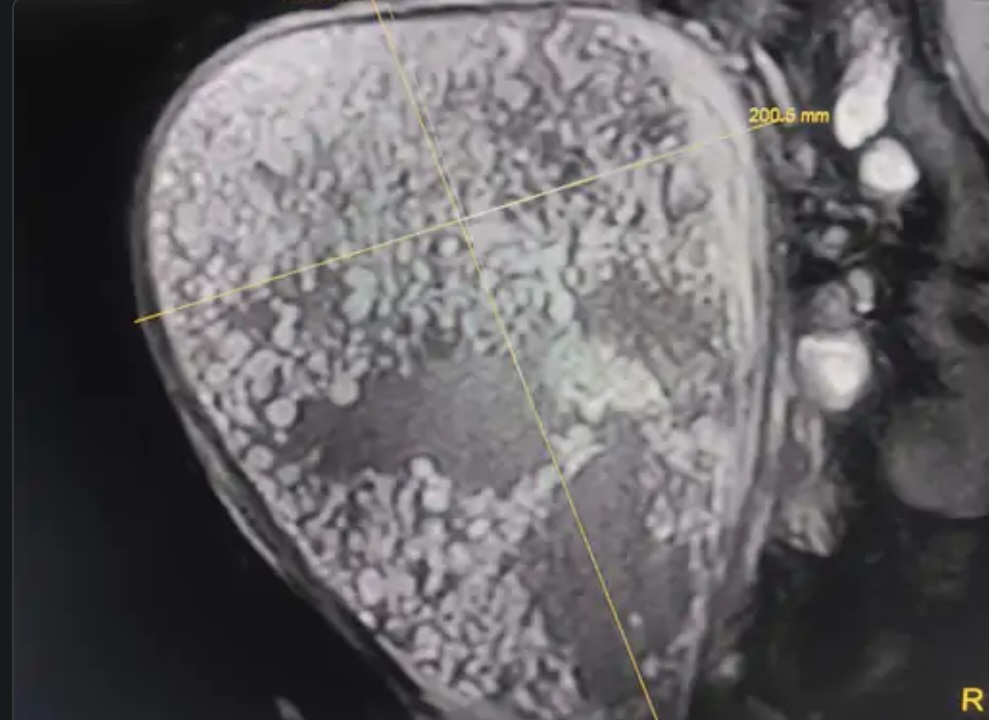

યુવતિની માતા કૂતૂહલવશ કેટલી વારમાં બાળક થઇ જશે ? તેમ પુછી રહી હતી. મેં તાત્કાલિક સોનોગ્રાફી કરતાં અજુગતુ લાગ્યુ હતું. પેટમાં બાળક છે જ નહીં, તેવું જણાવતાં બંને આશ્ચર્ય સાથે ચિંતામાં પડી ગયા હતાં. યુવતિના પતિ ત્રીજે મહિને અમારે ત્યાં ચેક કરાવ્યુ હતુ. ત્યારે બાળક હોવાનો રિપોર્ટ આવ્યો હતો.સાથે આવેલા સબંધીઓને આશ્ચર્ય પમાડે તેવી સ્થિતિ ઉદભવી હતી અને તેમને ભરોસો ન પડતાં યુવતિને MRI માટે મોકલી હતી. રેડિયોલોજીસ્ટ ડો.શિવાનીને પણ આશ્ચર્ય થયુ હતુ. પ્રેગનન્સી રિપોર્ટ નેગેટિવ આવતાં રાત્રે 11.30 વાગ્યે મને ફોન કર્યો હતો. મે લીટરેચર રિવ્યુ બાદ આ મોલર પ્રેગનેન્સી સાથે હુક ઇફેક્ટ હોવાનું જણાયુ હતું.જે જવ્વલે જોવા મળતી ઘટના હતી. આમ તો દર હજાર યુવતિએ એક યુવતિને મોલર પ્રેગનેન્સી થઇ શકે છે. પરંતુ 36 માસે મોલર પ્રેગનેન્સીનો આ પ્રથમ કિસ્સો હતો. એનેસ્થેટીક ડો.વ્રજેશ શાહની મદદથી યુવતિને બેભાન કરીને નોર્મલ પ્રસુતિ કરાવતા હોય તે પ્રમાણે પ્રસુતિ કરાવી હતી. આવા કિસ્સામાં યુવતિ ગર્ભવતિ તો થાય છે. પરંતુ ભ્રૂણનો વિકાસ થતો નથી. તે નાના પરપોટાની જેમ વિકસે છે.ગ્રામ્યની યુવતીને અગાઉ બે બાળક છે. જેથી ત્રીજીવખત પણ ગર્ભાવસ્થા દરમિયાન જણાતા લક્ષણો,ઉલટી અને પેટ ફુલવાની પ્રક્રિયા સિવાયની બીજી કોઇતકલીફ હતી નહીં. માટે તેણે સોનોગ્રાફી કરાવી ન હતીઅને ત્રીજુ પારણુ બંધાવાની આશામાં નવમા મહિને36 સપ્તાહનું ગ્રેવીડ યુટ્રસ અને મોલર પ્રેગેન્સસી મારા આઠ વર્ષના ગાયનેક કેરીયરમાં પ્રથમ ઘટના છે. સગર્ભા બહેનોએ ડેટીંગ સોનોગ્રાફી કરાવવી જોઇએ.